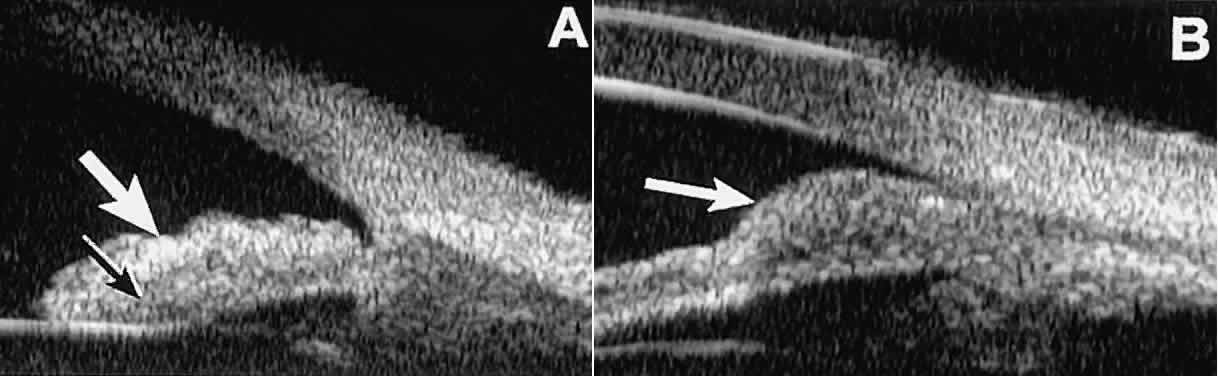

Fig. 26. UBM features of iris nevi. A. Superficial nevus appears as hyper-reflective layer of iris (white arrow). Normal iris stroma (dark arrow) is more sonolucent. B. Fusiform nevus of peripheral iris occupying full thickness of iris stroma (arrow). Note intact iris pigment epithelium underlying lesion.

In contrast, malignant melanomas of the iris and ciliary body are much less common. On UBM, such tumors are usually larger than benign nevi, and they are more likely to have caused focal or extensive disruption of the adjacent neuroepithelial layers, to have invaded the sclera, and to be associated with prominent intralesional blood vessels (Fig. 27). Some malignant melanomas of the ciliary body and most ciliochoroidal melanomas are too large in basal diameter to be fully revealed in a single UBM image, and many of these lesions are also too thick to be measured by this technology. In the case of a melanocytic tumor of the iris or ciliary body that is not clearly either a benign nevus or a malignant melanoma, serial UBM evaluations may prove useful for assessing the tumor's growth and other changes that might warrant either biopsy or complete excision of the mass.